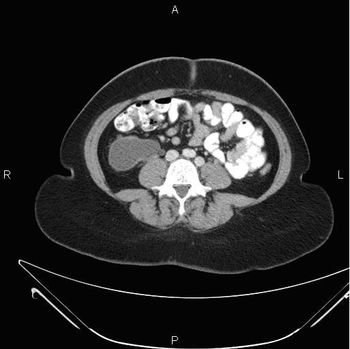

MSCT findings and histological feature correlations of pancreatic metastases from clear renal cell carcinoma.